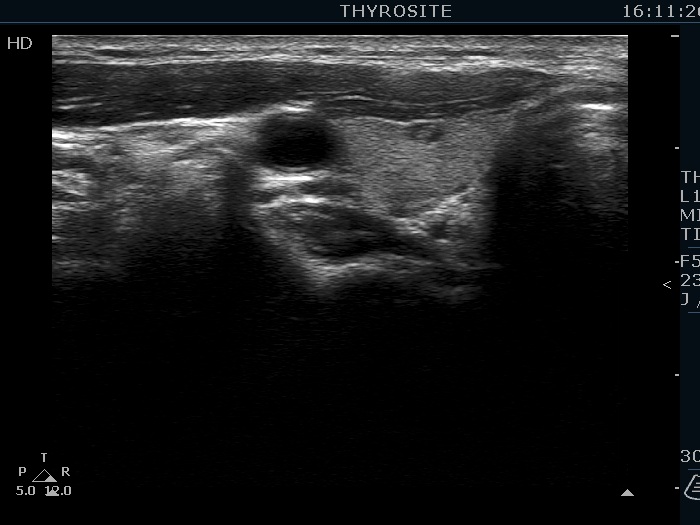

Ultrasonography. The thyroid was echonormal. There were several hypoechoic nodules in the left lobe. The middle one had back wall cystic figures. There were 3 or four discrete, deeply hypoechoic lesions above and lateral to the left lobe in the neck. One of them presented with a hilum-like figure while the others lacked hilum.